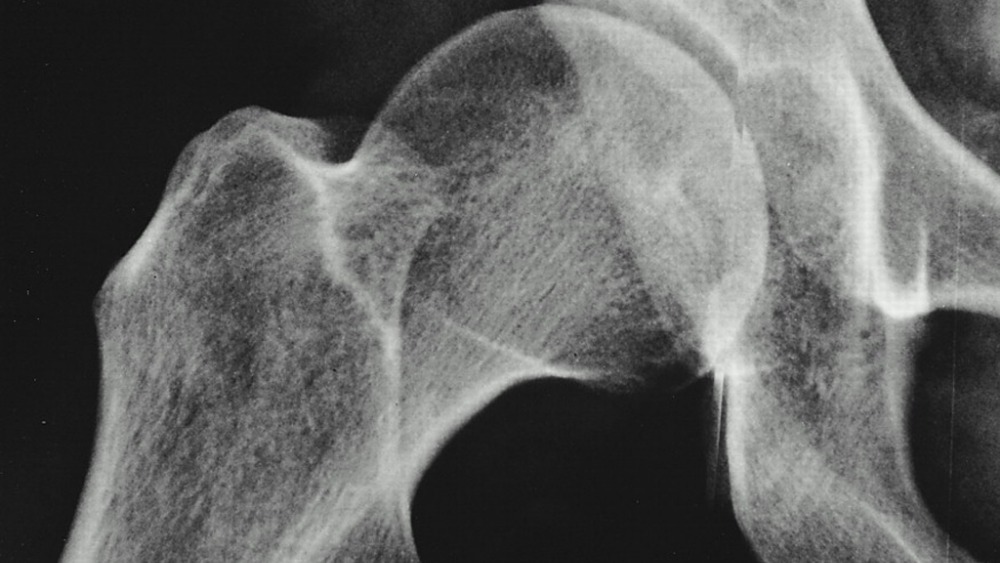

Xrays Before After Hip Replacement Surgery By Medical, 52 OFF

Xrays Before After Hip Replacement Surgery By Medical, 52 OFF What Are Nhs Hip Replacements Made Of A plastic (polyethylene) liner is usually used. The traditional type of replacement, which has been in use for many years, is a metal ball on a stem cemented into the femur (thigh) and a plastic socket cemented into the pelvis. Hip replacement surgery (sometimes called total hip replacement) involves replacing damaged parts of your hip joint with metal, plastic or.. What Are Nhs Hip Replacements Made Of.